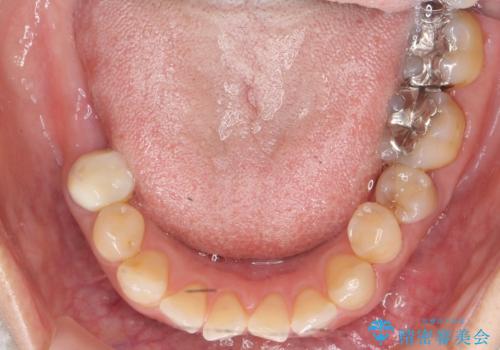

- 奥歯の痛みを主訴に来院された患者様です。

精査したところ、右下の奥歯(右下6)は割れており保存不可能な状態でした。

患者様のご希望により、右下大臼歯2本(右下76)のインプラント治療、右下小臼歯(右下5)の根管治療及び補綴治療を行いました。

割れていた歯の周囲組織の炎症が強く、骨の厚みが薄かったため、インプラント埋入時に骨増生(GBR)を行いました。